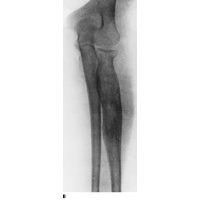

Plain film x-rays show a moth eaten lesion in the diaphysis. Lytic lesions are more common than blastic lesions and "onion skinning" may be present for sub-periosteal lesions.

Ewings sarcoma commonly presents in the lower extremety with femur 15-20%, pelvis 20%, humerus 5%, ribs 9-13%, spine 6-8%. Most present with localized disease but about 20-25% have lung mets, bone mets or bone marrow disease. Nearly all have micrometastases at diagnosis, so ALL get chemotherapy.